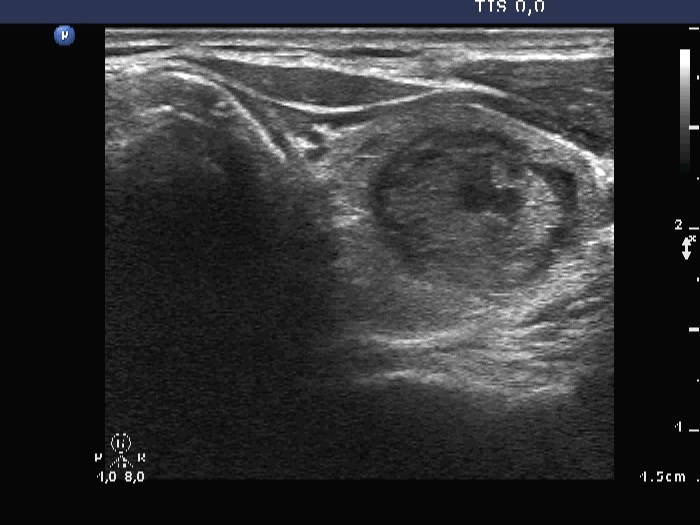

Papillary carcinoma - Case 10. (ultrasound picture 3)

Right lobe, horizontal view

Upper part of the left lobe, another horizontal view. There are bright hyperechogenic foci corresponding to non-specific granulations. Note that the solid part is echonormal.